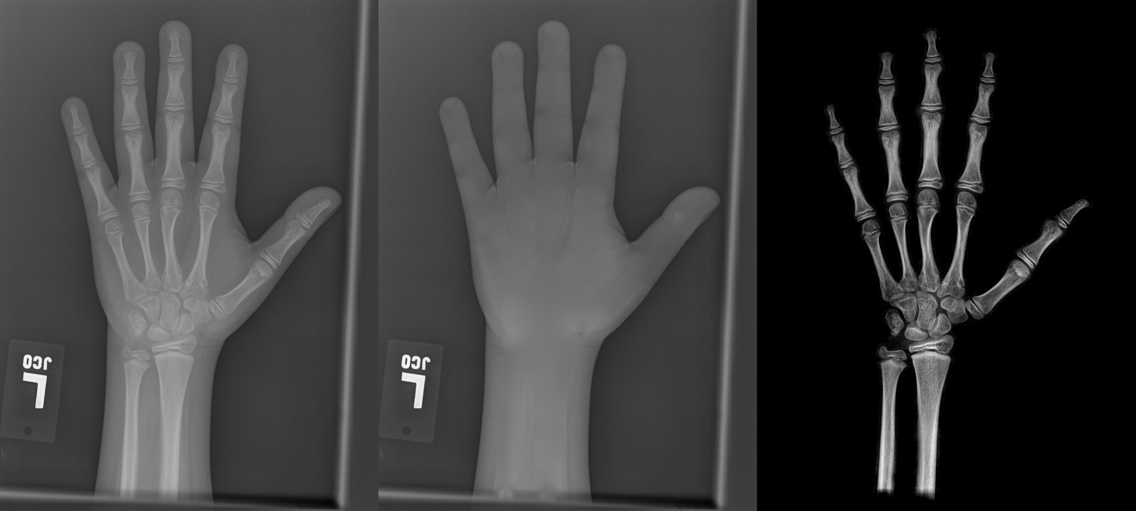

To tackle these problems, we propose to estimate the soft tissue image and bone image simultaneously without losing the linear relationship between image intensity and physical property of the imaging objects. Two examples from our method is shown in Fig. 1. The bone details are enhanced, which is theoretically guaranteed. The details of our method will be explained in later sections.

Several results from our method are shown in Fig. 7. The left column is the original input image. The right two columns are the soft tissue and bone image, respectively. It can be told that the soft tissue image is smooth as we assumed. Meanwhile, the bone image has better image contrast as desired. Moreover, our method can reach real-time performance on these X-ray images. The running time of our method on these images is reported in Table I.

In each panel of Fig. 10, the input image (left) is decomposed into soft tissue (middle) and bone image (right) by our method. Although we only show the first ten images from the data set, the results for the rest images are similar.

The bone images have better image contrast since the parameter is theoretically guaranteed. Such enhancement can also be directly told by radiologists. Such enhancement is good for bone diagnosis in practical applications.